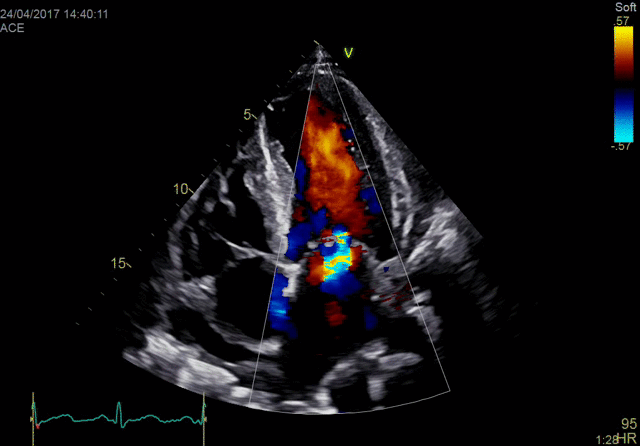

佳能Aplio 900 CV系统还在2018年推出了一种新方法,通过称为四腔室跟踪的回声可视化心脏。它在一个三维视图中跟踪所有四个腔室的血容量。它提供腔室的舒张末期和收缩末期视图。这允许一次完成整个心脏功能的图像,而不是一次查看一个腔室。